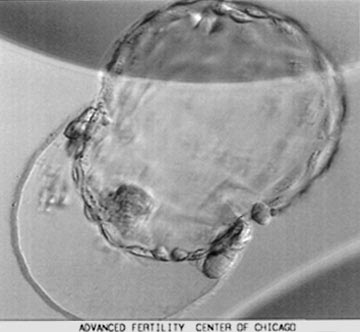

Хетчинг эмбрионов что это

Хетчинг эмбрионов что это 108 фото